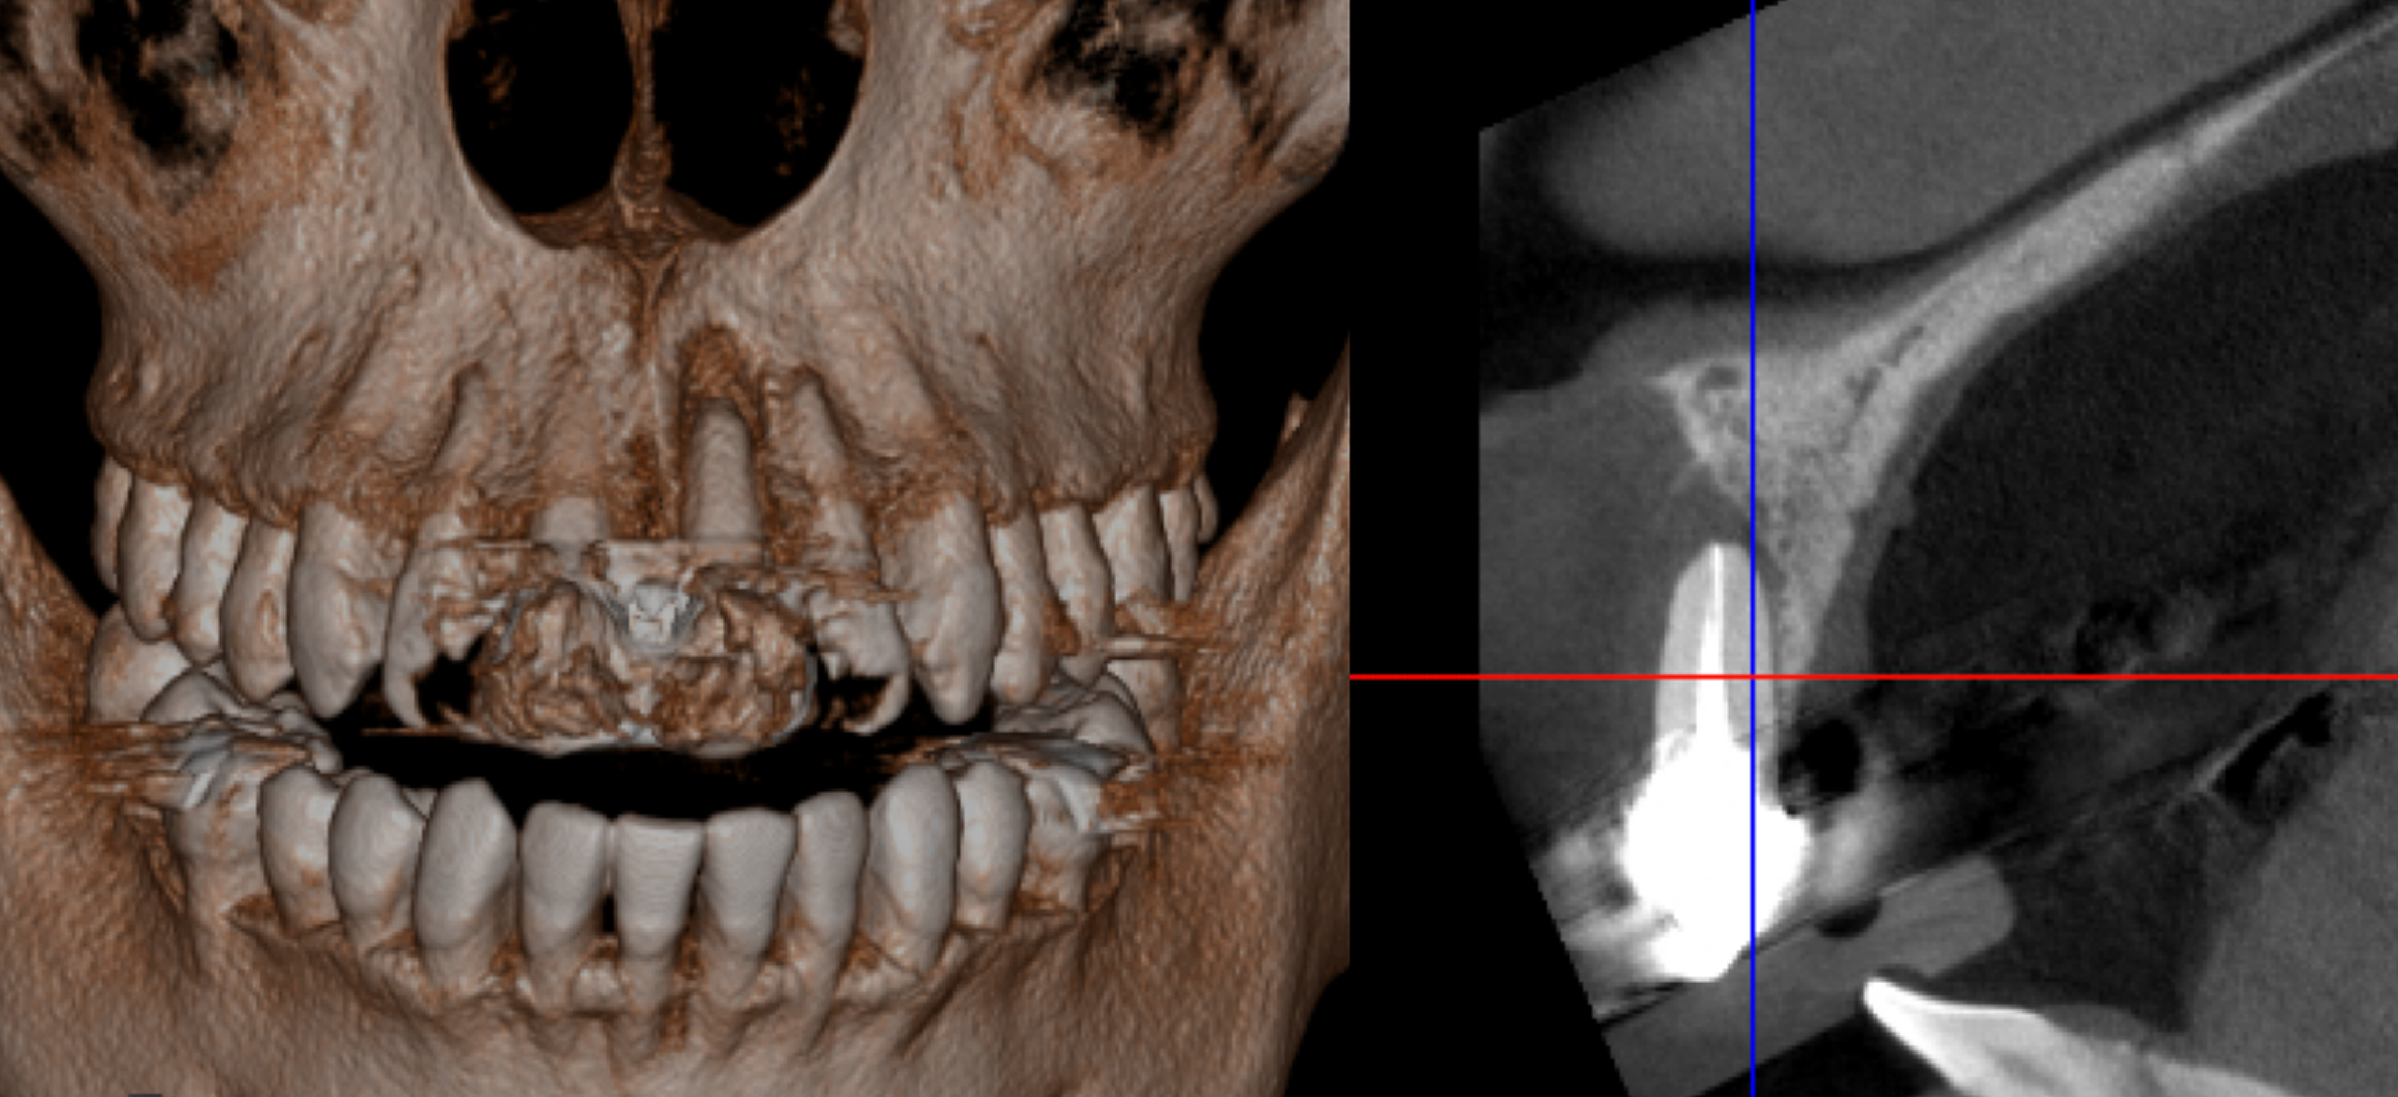

左上は歯の周りに骨が全然なかったので抜歯後に骨を作る処置(GBR)を行いました。

緑部分が作った骨になります。半年間待ちましたが、これがないと仕上がりが長い歯になってしまい、すごく見た目が悪くなってします。

デジタルシミュレーションを駆使したことで、術前の「生理的咬合である」という診断に基づいた精密な治療計画の立案が可能となりました。